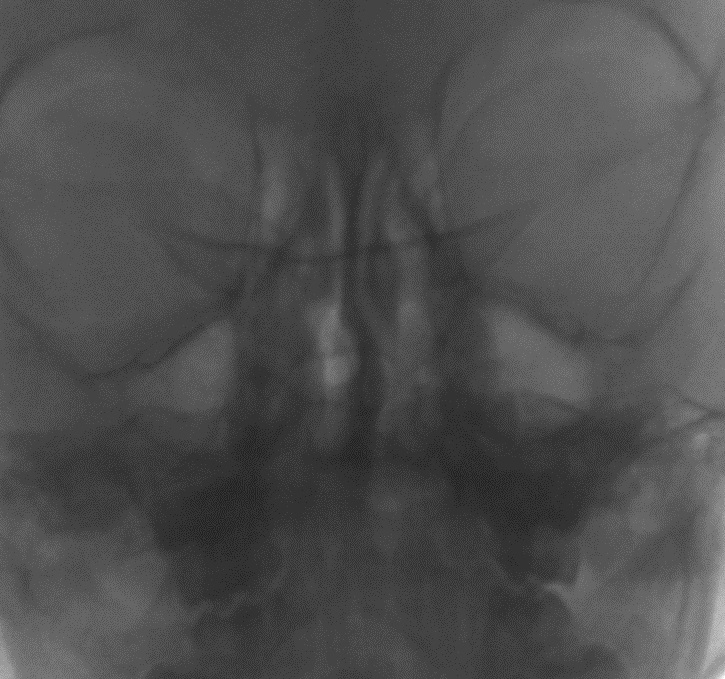

Острый гнойный процесс в гайморовой пазухе

По результатам осмотра выявлена патология придаточных пазух носа. По рекомендации ЛОР-врача сделан низкодозовый цифровой снимок придаточных пазух в присутствии родителей, благодаря чему маленький пациент чувствовал себя в безопасности и не мешал проведению исследования.

Выявлен острый гнойный процесс в гайморовой пазухе. Ребёнок получал соответствующее лечение по строгой схеме.